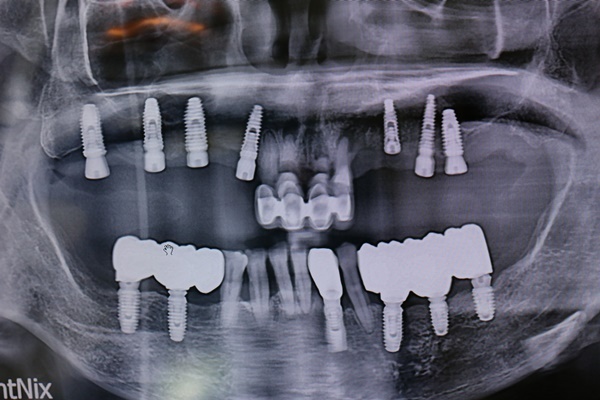

當成功的把植牙放在牙床裡,基本上是可以承受跟過去自然牙的咀嚼能力接近,但它沒有辦法像自然牙有宛如「懸吊系統」的牙周韌帶,所以植牙在咬合上的考量,還是要有一些經驗跟技巧。

自然牙萬一碰到一個撞擊,或是突然咬到一個堅硬的東西,因為有牙周韌帶的機制,會把這力量做分散;但植牙就可能直接硬碰硬了。

沒有牙周韌帶的植牙,就如同是缺少懸吊系統的緩衝,植入的牙在面臨到比較突然過度的壓力、意外受傷,會比較容易傳導到骨頭深處,造成不必要的傷害。所以建議在做完植牙的假牙之後,要有慢慢去適應的觀念,特別是過去缺牙時間比較久,植牙的重新製做,雖然能替代缺失牙,但也的確需要臉頰肉、舌頭以及對咬牙來慢慢適應,一般很少人馬上就覺得「用起來很順」,除非剛拔完牙不久就植牙記憶猶新。